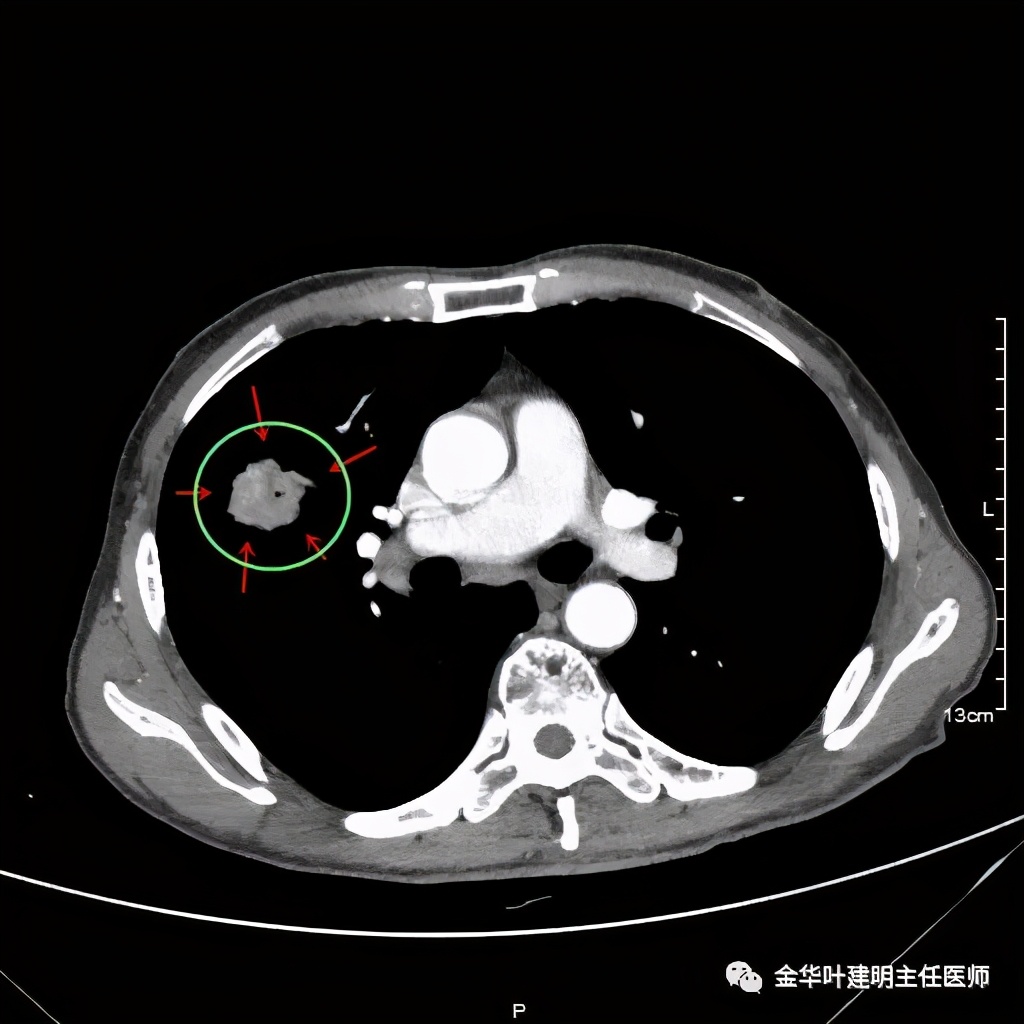

上图示纵隔窗实性

上图示纵隔窗密度不均

上图示纵隔窗病灶有膨胀性,内部有强化较明显的条索状(新生血管?)

上图示纵隔窗病灶表面欠平整,中间有小空洞,密度不均,局部似有坏死(空洞旁边)

上图示病灶强化不等,表现不平,中间有空洞,空洞旁边有偏低密度区(坏死?)

上图示病灶膨胀分叶,表面不平,像个土豆

上图示病灶密度不均,有偏低密度的区域

上图黄色箭头示空洞形成,病灶表面不平